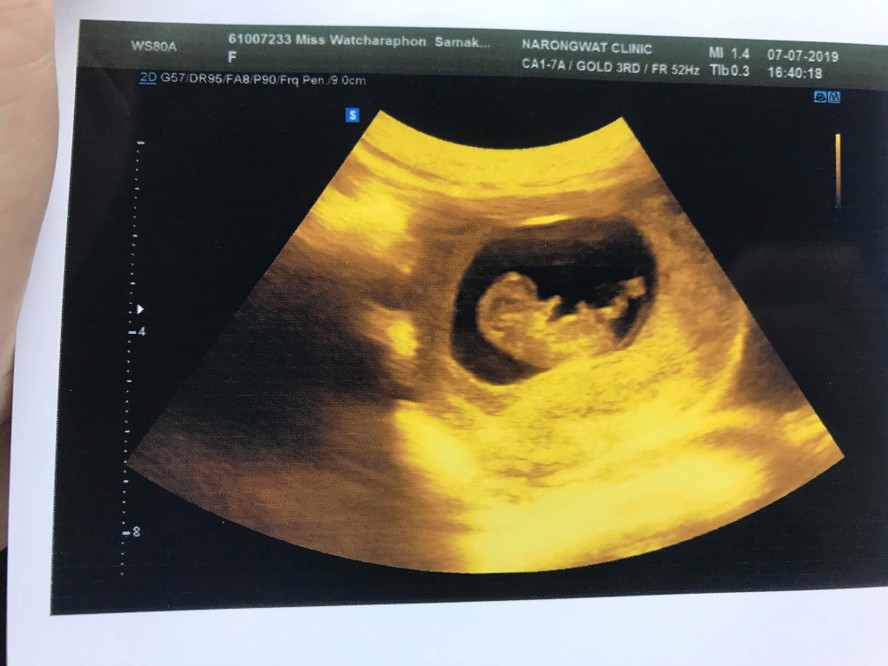

ตอน10สัปดาห์2วันค่ะ